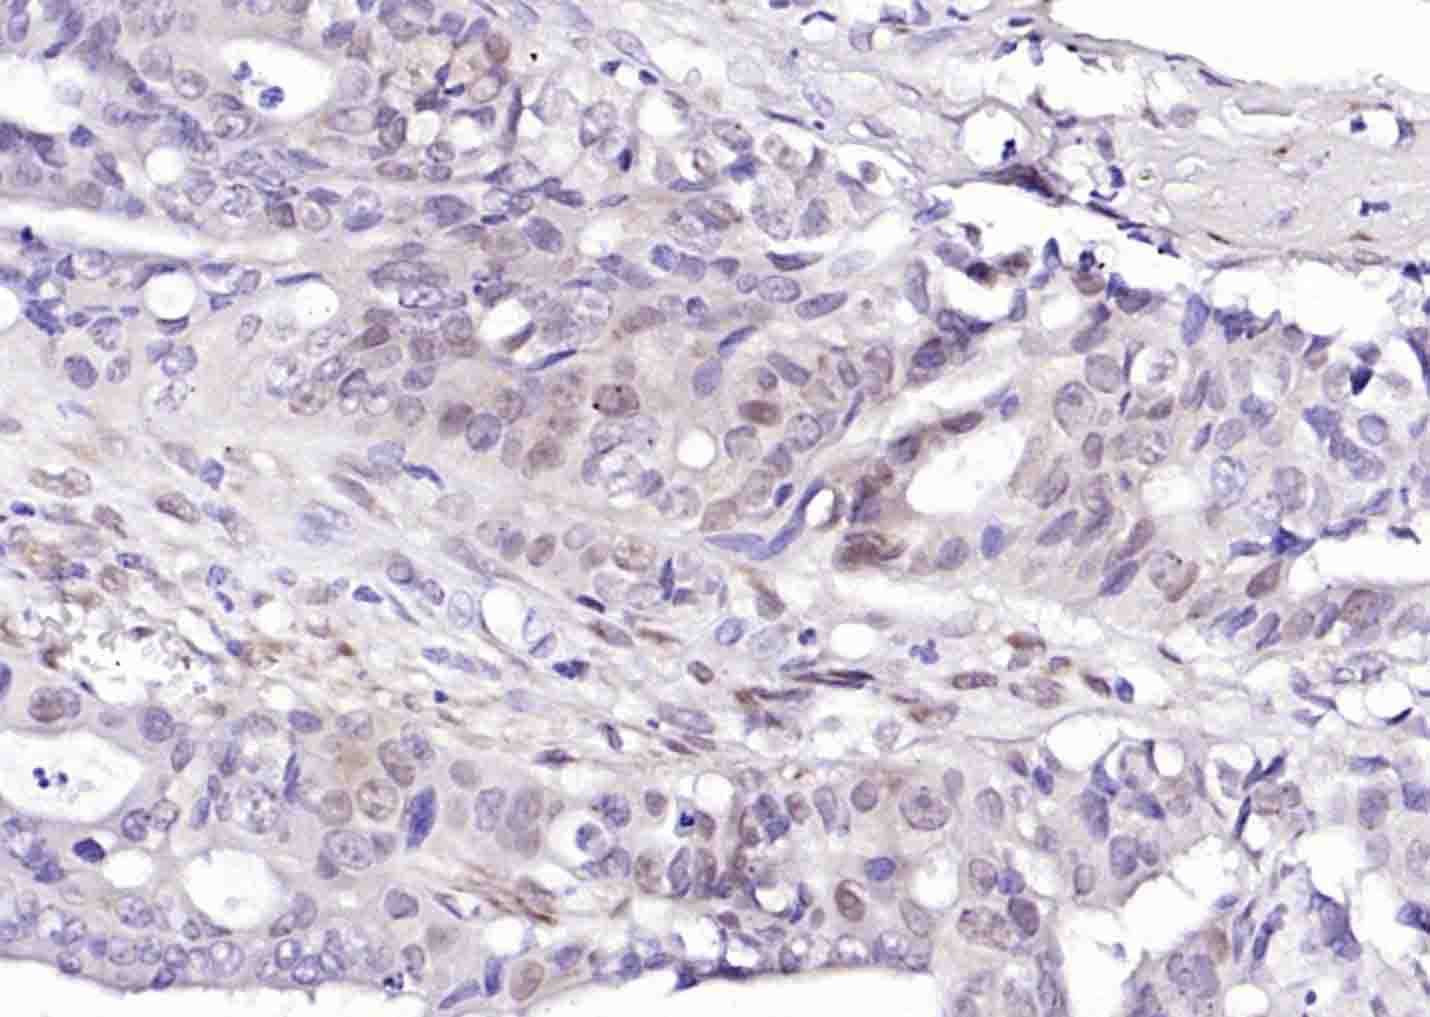

| IHC-P | Human, Mouse | Rat | 1:100-500 |